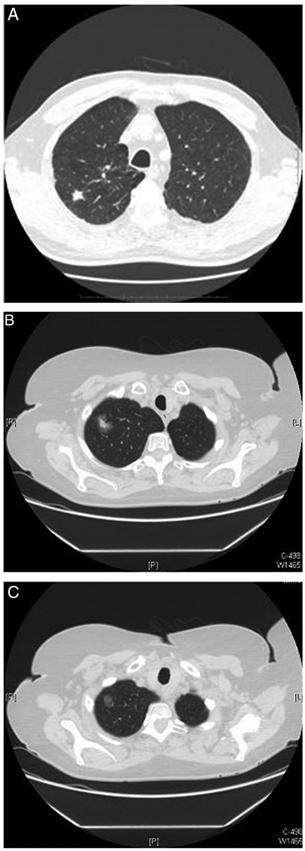

结节的形态分为实性或亚实性,亚实性结节可进一步分为纯磨玻璃结节(无实性成分)和部分实性结节(含有磨玻璃成分和实性成分)(见下图)。

目前有多种软件可以计算被筛选出的结节的体积大小,被称为半自动体积分析(见下图),体积增长超过25%被认为是有意义的。